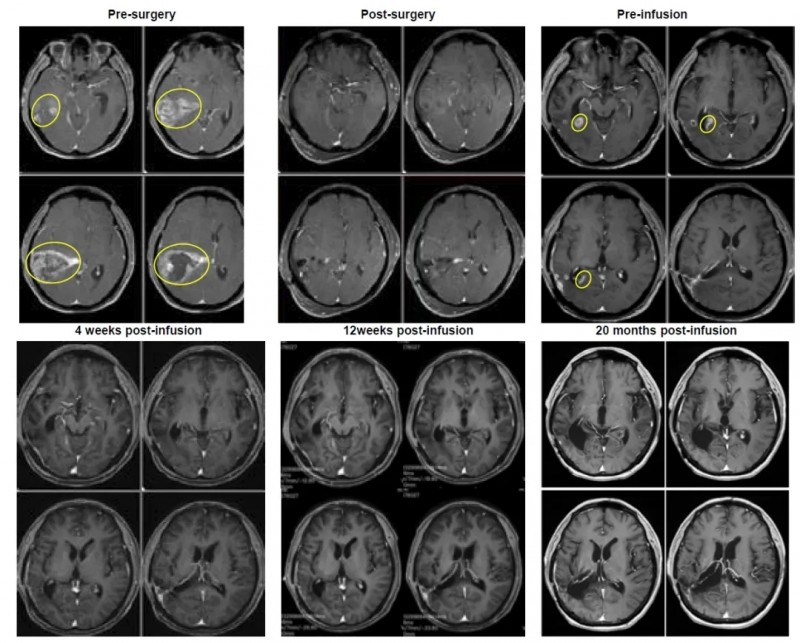

该幸运患者是一位56岁男性,确诊为左侧额叶胶质母细胞瘤(IDH野生型,WHO4级,EGFR扩增):2023年1月接受肿瘤切除术后,经Stupp方案治疗病情短暂稳定后复发;后续虽接受了针对IL-13Rα2和B7-H3两种抗原的17次CAR-T治疗,病情仍持续进展。最终患者入组TIL临床试验,研究团队先从其初始手术切除标本中,成功制备TIL细胞;再经预处理后,为患者进行了TIL细胞输注。

结果显示:输注前患者复发病灶最大直径达2.8cm,而输注后4周(2024年1月8日),肿瘤被完全切除;截至2025年9月9日,患者已维持完全缓解状态超过1.8年,持续获益显著(详见下图)。

▼该患者治疗过程中的磁共振成像(MRI)图像。

▲图源“BMJ”,版权归原作者所有,如无意中侵犯了知识产权,请联系我们删除

综上,该研究证实,即便胶质母细胞瘤被归类为“冷肿瘤”,其肿瘤浸润淋巴细胞仍可在体外有效扩增;而颅内病灶的完全缓解,更直接证明了TIL细胞具备穿过血脑屏障的关键能力——这一突破解决了脑瘤治疗的核心难题之一。从CAR-T到TIL疗法,免疫治疗正持续突破脑癌治疗的“禁区”,为晚期脑瘤患者带来了新的希望和选择!更重要的是,从患者早期手术切除组织中提取的TIL细胞,成功实现了复发性肿瘤的缓解,这凸显了早期留存肿瘤组织标本,对复发性GB患者后续接受TIL治疗的重要临床价值。